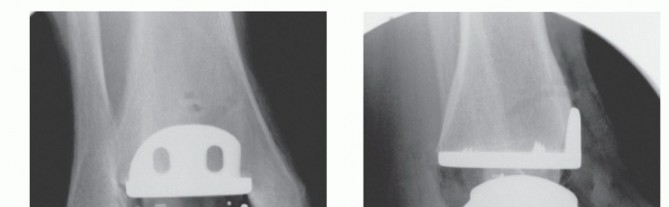

It is furthermore highly recommended to check the position of the implants by fluoroscopy, as described earlier for the trial implants (TECH FIG 4E,F). This allows the surgeon to detect any remaining bony fragments or osteophytes that could be a potential source of pain or motion restriction.

TECH FIG 4 • (continued) E. Final check of the position of the implants using fluoroscopy. On the AP view, the surgeon checks the position of the implants for any misalignment that may cause edge load of the polyethylene insert, overall alignment in the frontal (coronal) plane, distraction of the ankle (gap between the fibula and talus), and medial and lateral gutters for any bone left that may cause bony impingement. F. On the lateral view, the surgeon checks the position of the implants with regard to the bone surfaces (proper fit) and alignment of the implants with regard to contact area (usually, the apex of the talar component should meet the tibial component 3 to 5 mm anterior to its midpoint). 3. ## Wound Closure